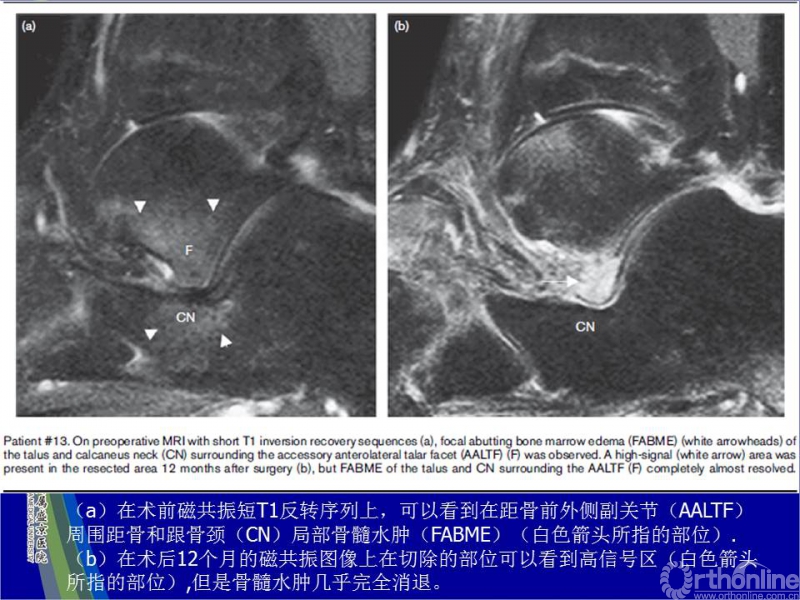

3. 临床表现为行走时跗骨窦区疼痛。CT或磁共振提示距骨前外侧副关节的存在,同时排除跗骨联合。磁共振显示副关节周围距骨和跟骨颈部水肿